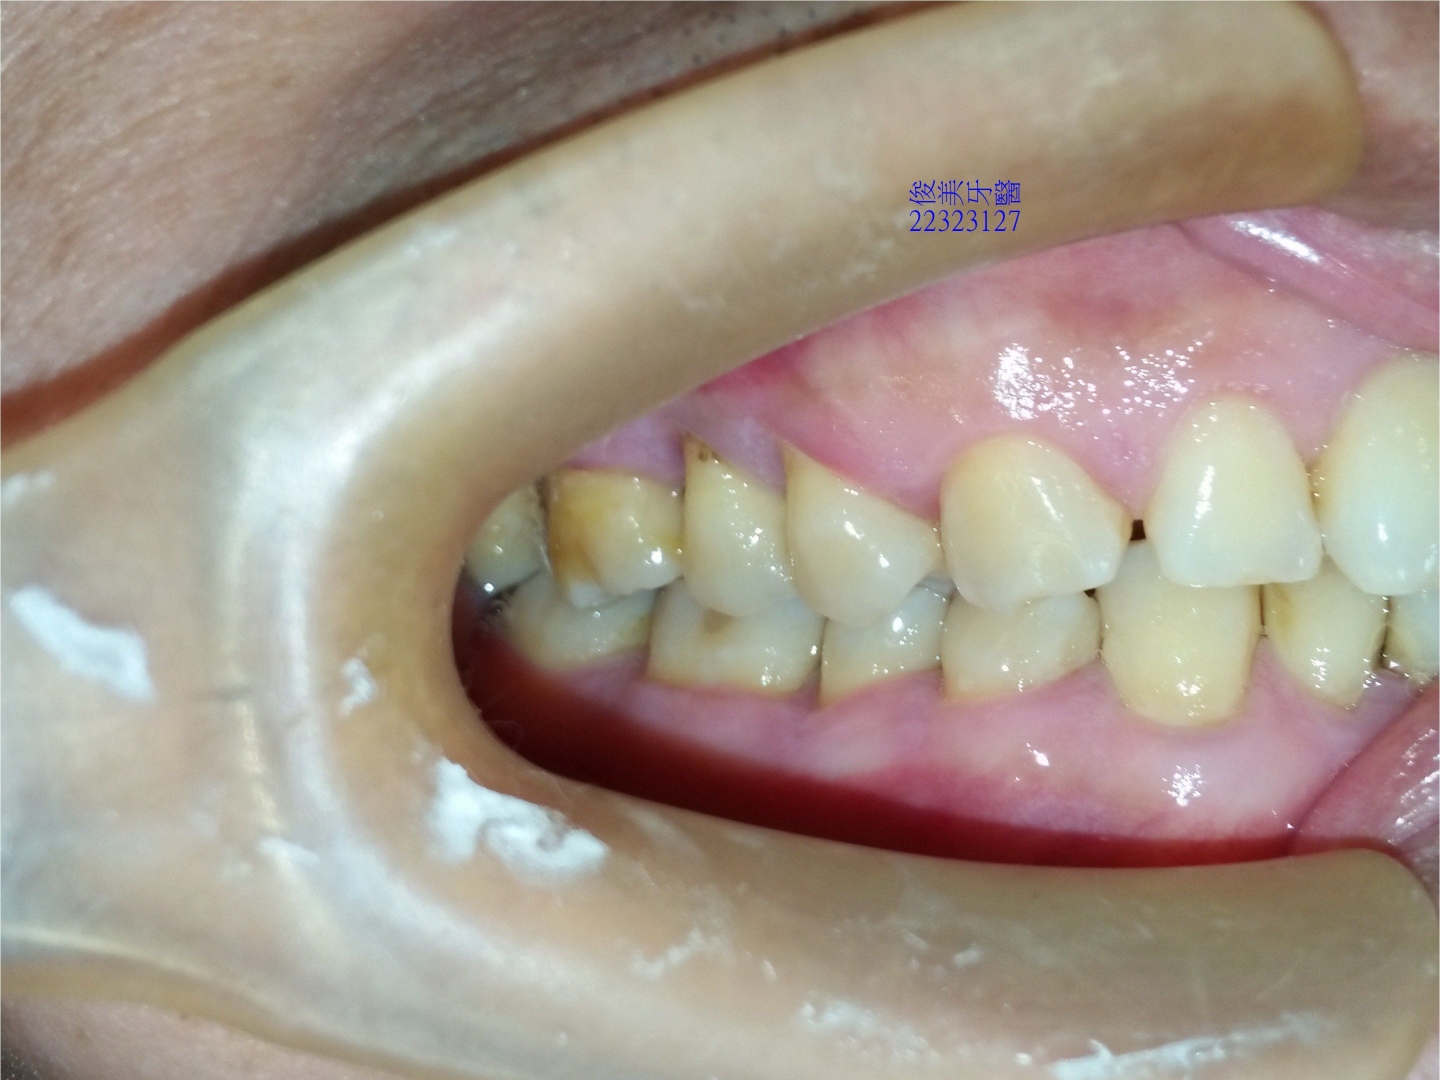

下顎原始狀況。牙齒開始內傾到舌側位置。

後牙咬合高度逐漸變低。

後牙咬合高度逐漸變低;犬齒受力大,高度剩下2/3,切端皆已磨損喪失。